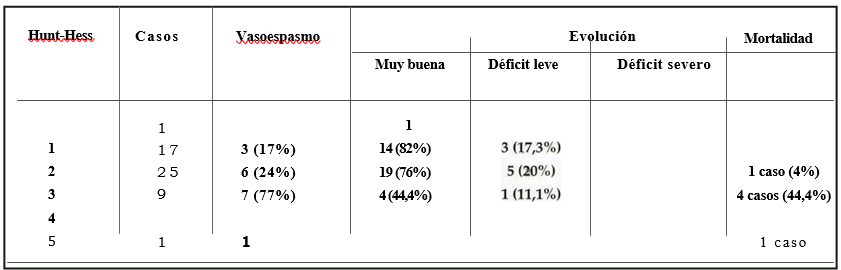

Del análisis de la evolución de los pacientes (Tabla 6) surge una evidente relación entre su ubicación en el score de Hunt-Hess y en la escala de Fisher tomográfica, factores ambos relacionables con la frecuencia de vasoespasmo.

Tabla 6. Correlación grado de Hunt-Hess vs. Vasoespasmo y resultados.

Los porcentajes están expresados en relación a cada grado en particular

En el grado I se ubicaron 17 casos (32%), que se distribuyeron en la escala de Fisher de la siguiente manera: Fisher I, ningún caso; Fisher II, 12 casos Fisher III, 2 casos y Fisher W, 3 casos. Tres pacientes desarrollaron vasoespasmo en este grupo (17%). Registramos una muy buena evolución (sin déficit) en 14 pacientes (82%) y una buena evolución (déficit menor), en 3 pacientes, los síntomas fueron transitorios y debidos al desarrollo de vasoespasmo. No se produjeron casos de discapacidad grave ni de mortalidad.

Incluidos en el grado II, fueron tratados 25 pacientes, de ellos tuvimos 19 casos (76%) con muy buena evolución, 5 casos con déficit menor (20%) y un paciente falleció (mortalidad del 4%). Desarrollaron vasoespasmo 6 pacientes (24%).

En el grado III, con 9 pacientes, 7 presentaron vasoespasmo (77%) que coincidían con un Fisher tomográfico de 3 y 4. De este grupo 4 pacientes tuvieron una muy buena evolución (44,4%), un paciente presentó un déficit menor (11,1%) y 4 fallecieron (44,4%).

Dentro del grado IV no se presentó ningún paciente y con grado V tuvimos un caso que ingresó en coma profundo con anisocoria, rigidez de descerebración y en la TAC se observó un hematoma temporal. El enfermo fue intervenido de urgencia falleciendo al octavo día.